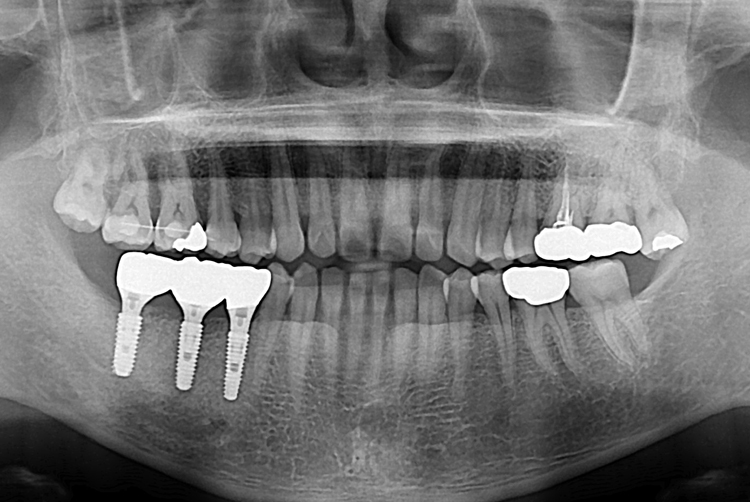

[임플란트] 어금니 임플란트

치료후 : 2019-10-23

세종치과는 많은 환자와 다양한 케이스를 바탕으로

항상 편안한 임플란트 수술을 제공하고자 노력하고,

오래동안 튼튼히 쓸 수 있는 임플란트 수술을 가장 큰 목표로 삼고 있습니다.